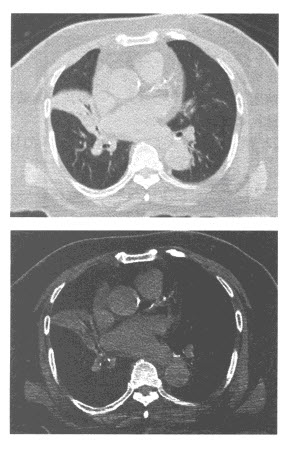

女,23岁,胸闷、气促1个月余,左侧锁骨上触及无痛性肿大淋巴结。胸部CT增强扫描片如图,最可能的诊断为()

A.淋巴瘤

B.肺动脉栓塞

C.右上肺肺癌

D.非侵袭性胸腺瘤

E.结节病

血友病患者突发胸闷,气急,体查见颈静脉显露,嘴唇发绀,影像学检查如图,最可能的诊断为()

A.纵隔自发性出血

B.淋巴瘤

C.结节病

D.纵隔积液

E.胸腺瘤